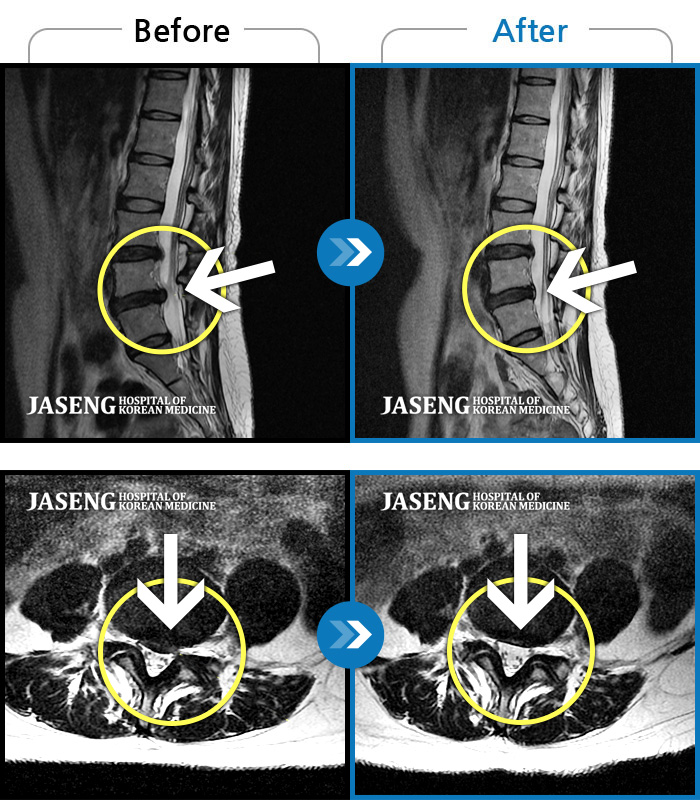

ȯںп Ǹ ǿ ԿǾ, ο ġ ۿ Ƿ ġḦ Ͻñ ٶϴ.